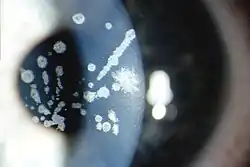

Granular corneal dystrophy type II, Variable sized crumb-like opacities in the corneal stroma that have become fused in areas giving rise to elongated and stellate shapes

Granular corneal dystrophy type I, Numerous irregular shaped discrete crumb-like corneal opacities